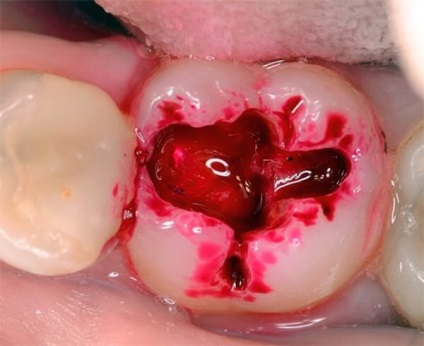

Diagnosticarea cariilor dentare este produs nu numai prin utilizarea de hardware sau de examinare instrumentale. Pentru a determina gradul de implicare a țesutului în procesul patologic, atât înainte de începerea tratamentului și în timpul procedurii, folosind un marker anticarii.

Mijloacele pot fi utilizate pentru determinarea cariilor pe o suprafață smalț și în regiunea cavității dintelui pregătit.

Datorită componentelor speciale care alcătuiesc mijloacele, lichidul este reținut numai pentru țesuturi demineralizat. smalț sănătos și dentina nu se schimba culoarea lor. Cu markerul de suprafață pot fi îndepărtate cu ușurință nu numai apa, ci, de asemenea, un tampon obișnuit.

Pentru a spori efectul de colorare în timpul preparării, este necesar în mod periodic pentru a influența această zonă direcția de moment a aerului cald. Absența suprafața vopsită după aplicarea unui marker, spune că toate smalțului afectat și dentina au fost eliminate.

Proprietățile unice ale țesutului pigment pata la nivel celular, permite identificarea tesutului demineralizate nu numai slab, dar, de asemenea, necrotizantă complet dentina, situate adanc in cavitatea dintelui.

În cele mai multe cazuri, purificarea incompletă a dentinei mort duce la dezvoltarea cariilor secundare. în curs de dezvoltare sub sigiliu.